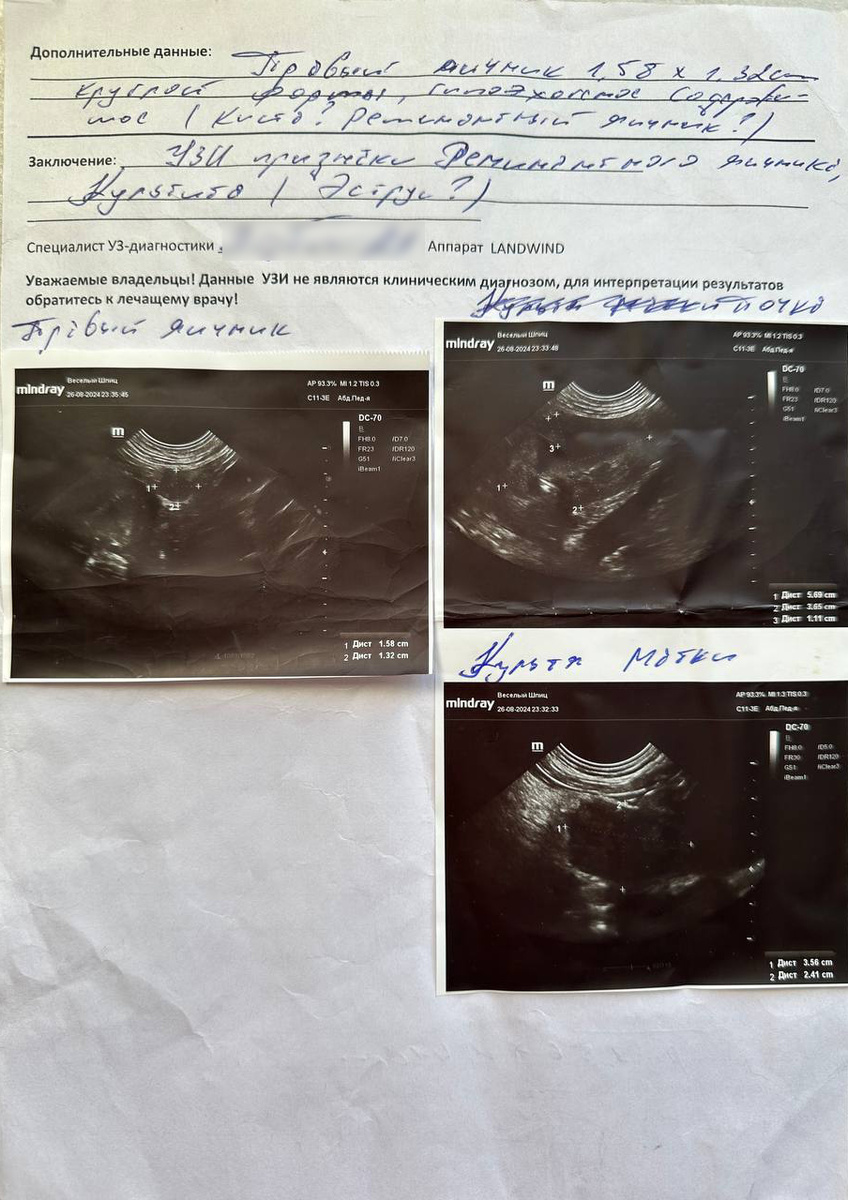

И правда, собака восстановилась очень быстро, разрез крошечный. ВАЖНО: по мнению ветеринаров, с которыми я общалась позже, техника считается устаревшей, к органам добраться очень сложно, часто удаляют не все. Так и произошло с нами. Меньше, чем через год у Сансы началось что-то похожее на течку. Как только обнаружили кровянистые выделения, экстренно ночью повезли ее на УЗИ брюшной полости, которое показало, что не удален правый яичник.

Первое УЗИ, которое показало, что оставлен правый яичник.